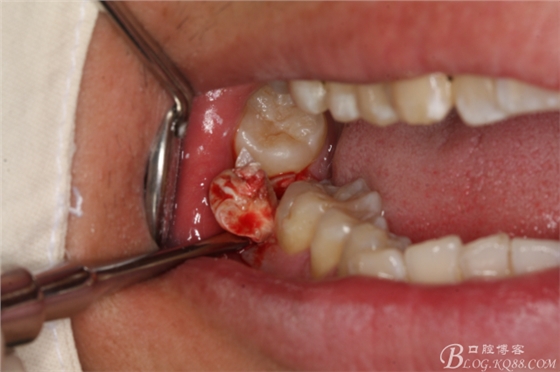

圖8.先橫斷47牙冠,盡量從牙頸部橫斷

圖9.潛掘法橫斷牙冠

圖10.橫斷牙冠的影像

圖11.牙挺分開(kāi)47牙冠